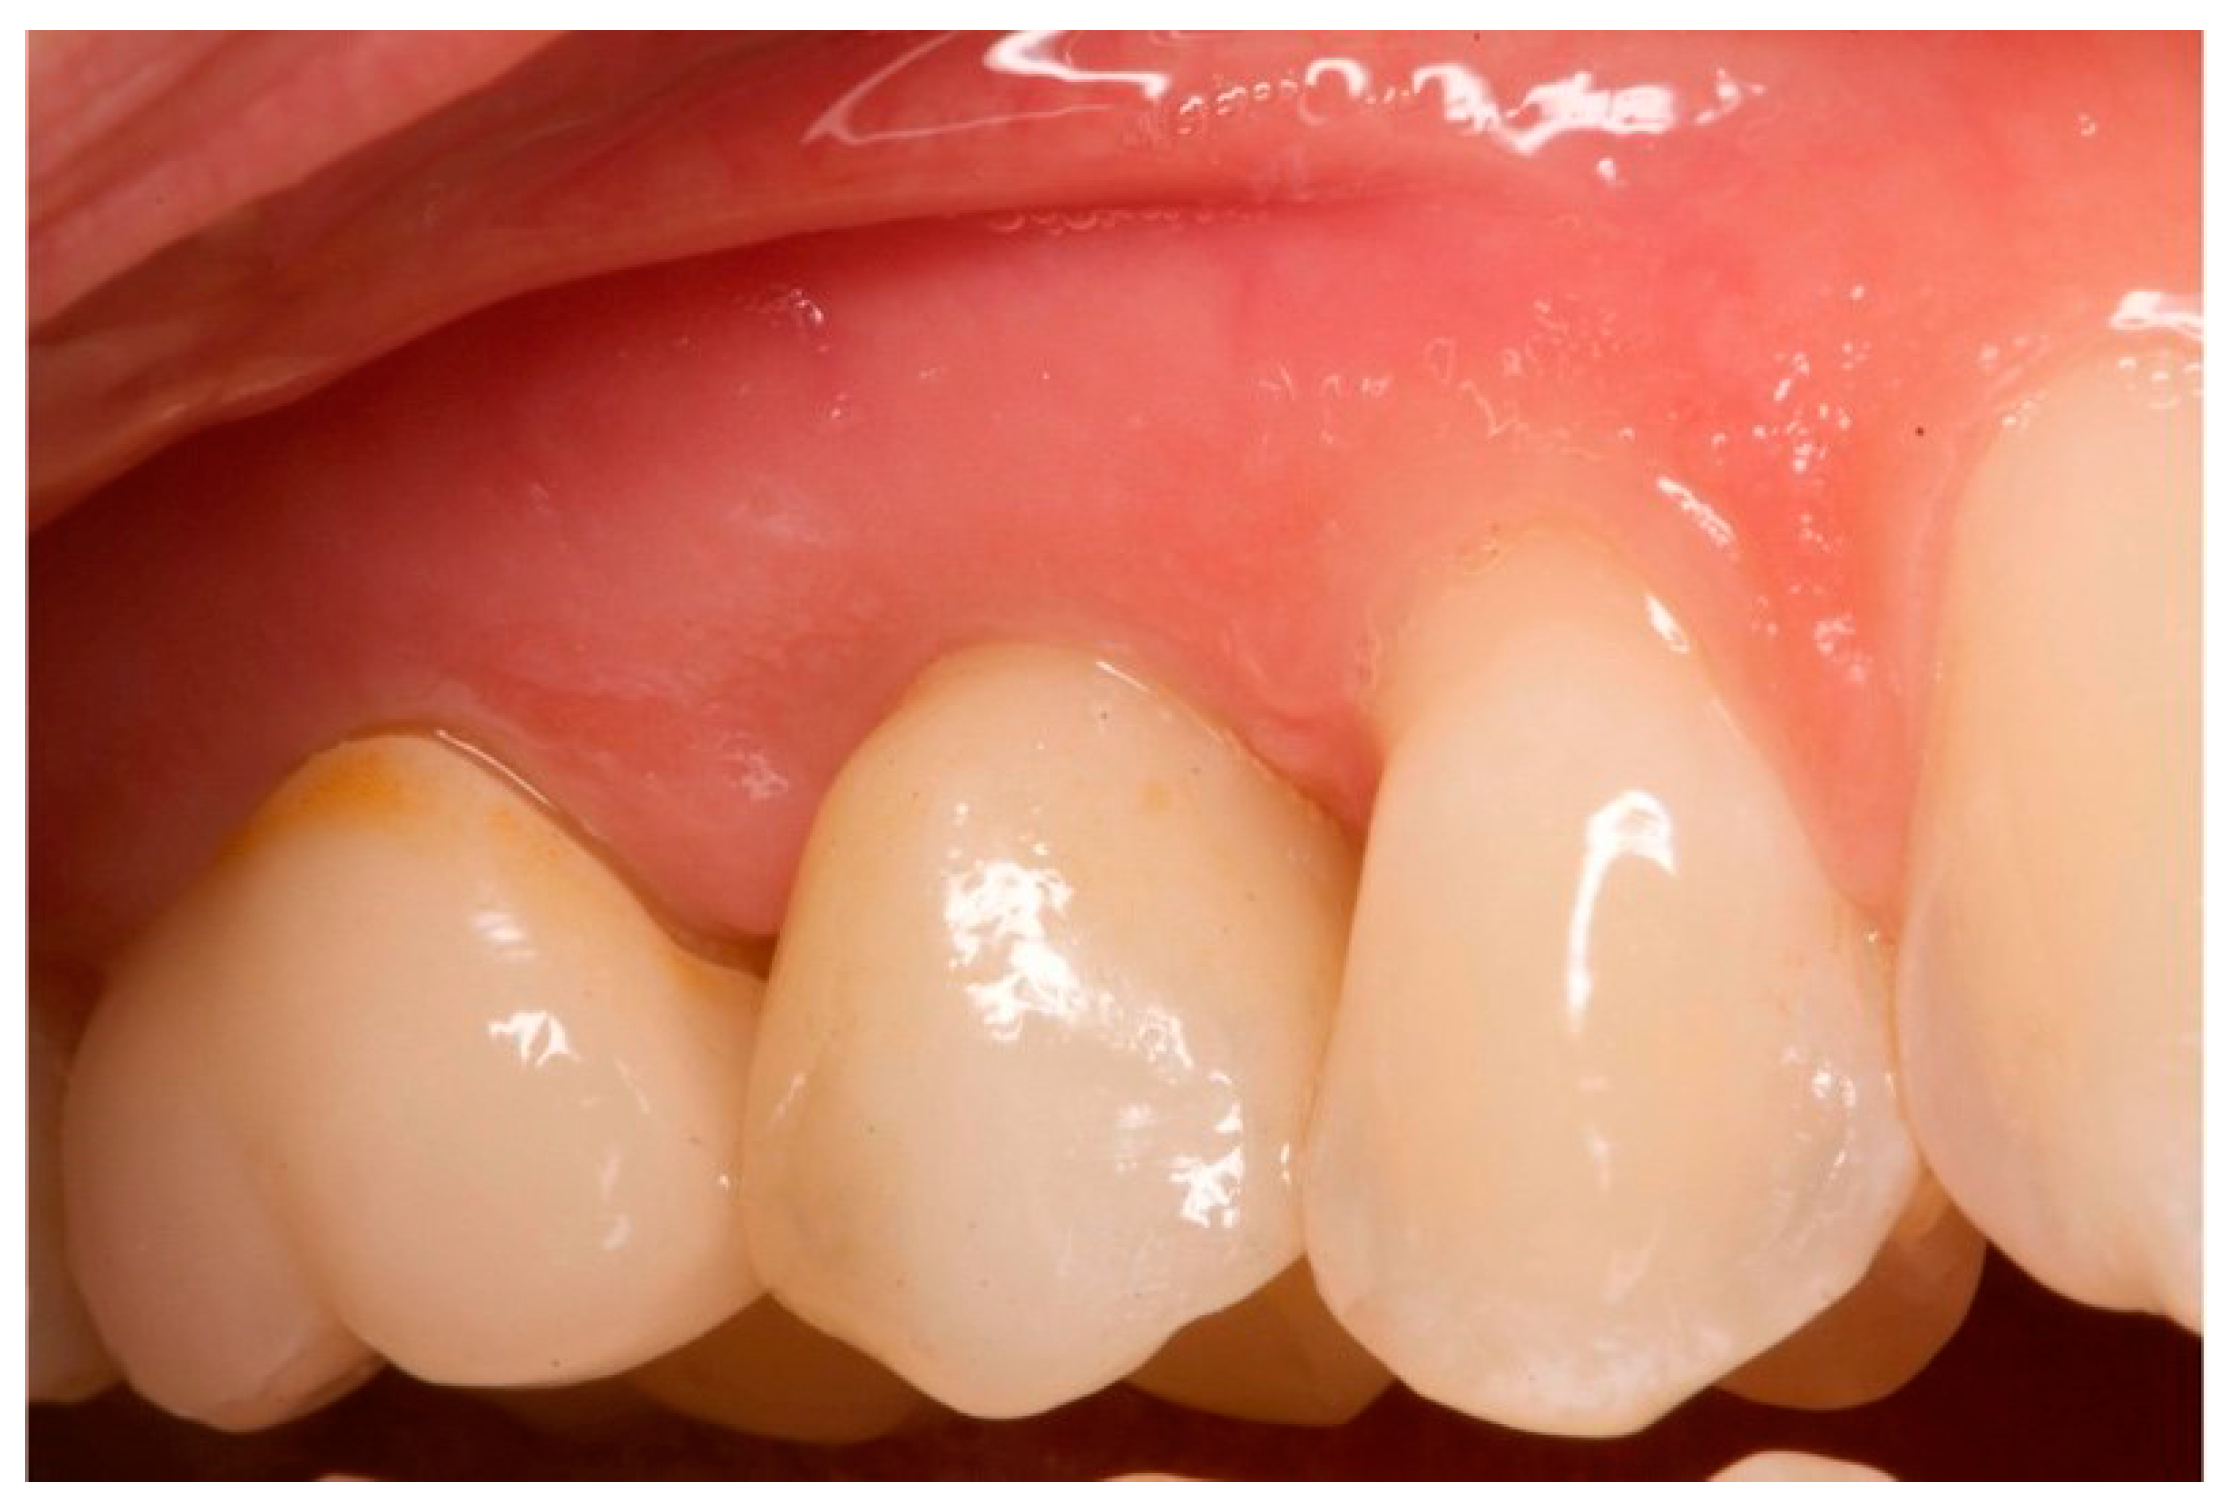

Figure 15.

One-year follow-up. Element 1.5.